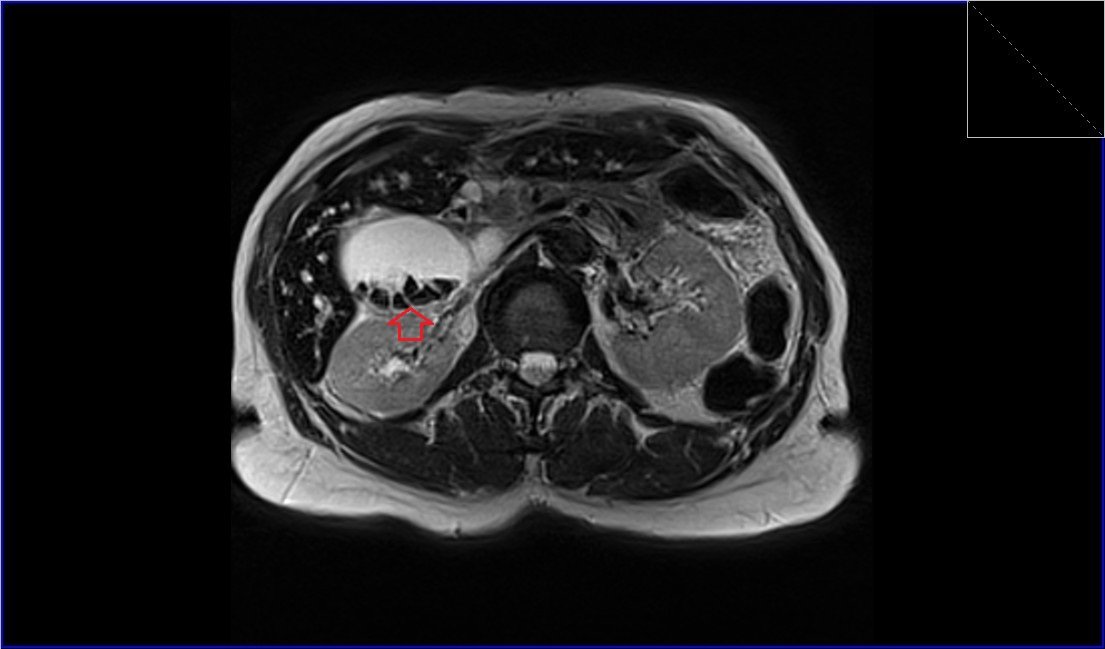

MRI abdominal pathologies FNH LIVER Haemangiomas Liver Choledocholithiasis Renal cell carcinoma Abdominal Wall AVM Gallstones Retroperitoneal desmoid Hepatocellular carcinoma (HCC)